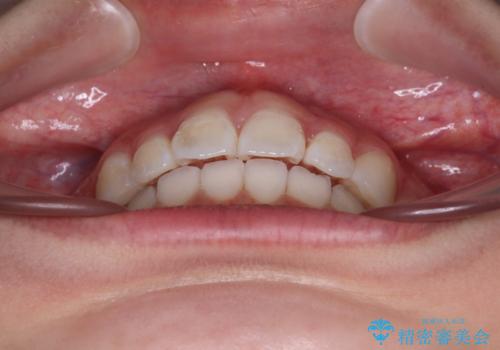

- 上下前歯の叢生を気にして来院された患者様です。

インビザラインでの治療を希望されていて、デコボコの程度が中等度であり、安価なパッケージにて対応可能と判断されたため、インビザライン・モデレートを用いて矯正治療を行うこととしました。

インビザライン・モデレートは、製作できるアライナーの枚数に制限があるため、移動可能な量に限りがあるものの、インビザライン・ライトよりも枚数が多いため、幅広い症例に対応可能です。